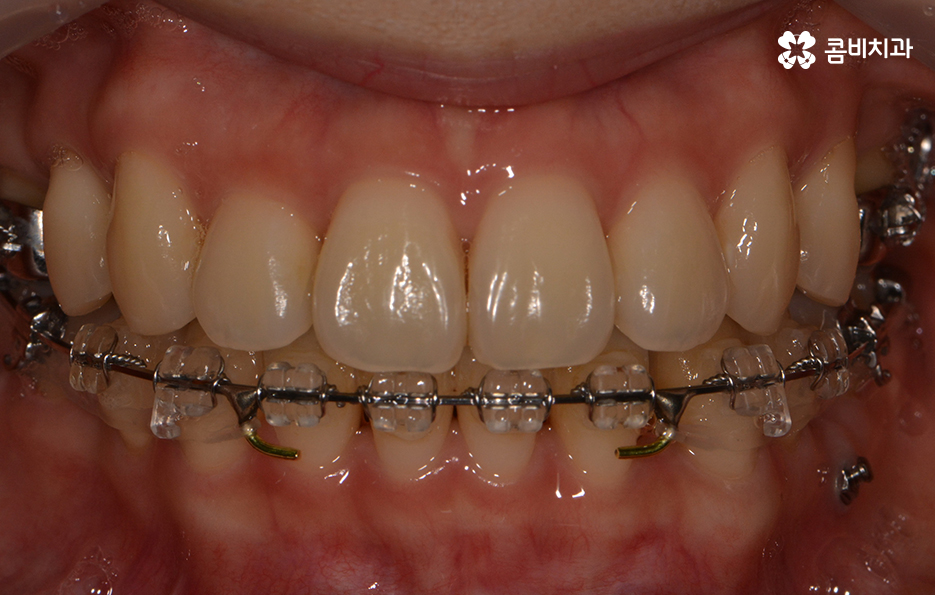

돌출된 앞니로 인해서 교정을 원하신 상황이며 치료 전 치아 상태

치열의 상태가 정면으로 바라봤을 때 비교적 가지런한 편이지만

측면으로 볼 때 유독 앞으로 돌출된 경우라면

입모양과 얼굴형에도 영향을 주기 때문에

앞니치아교정을 알아보시는 분들 중에서

이러한 고민으로 인해 치료를 원하시는 경우가 많습니다.

치료가 시작되기 전 치아 상태